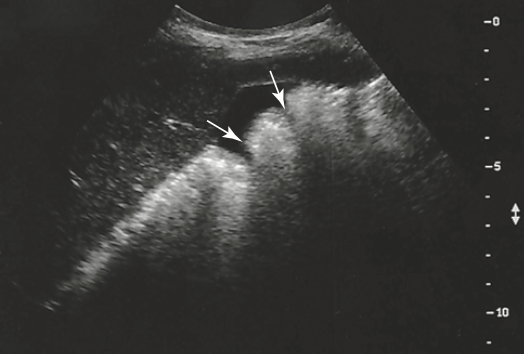

what are the arrows point to

haustra